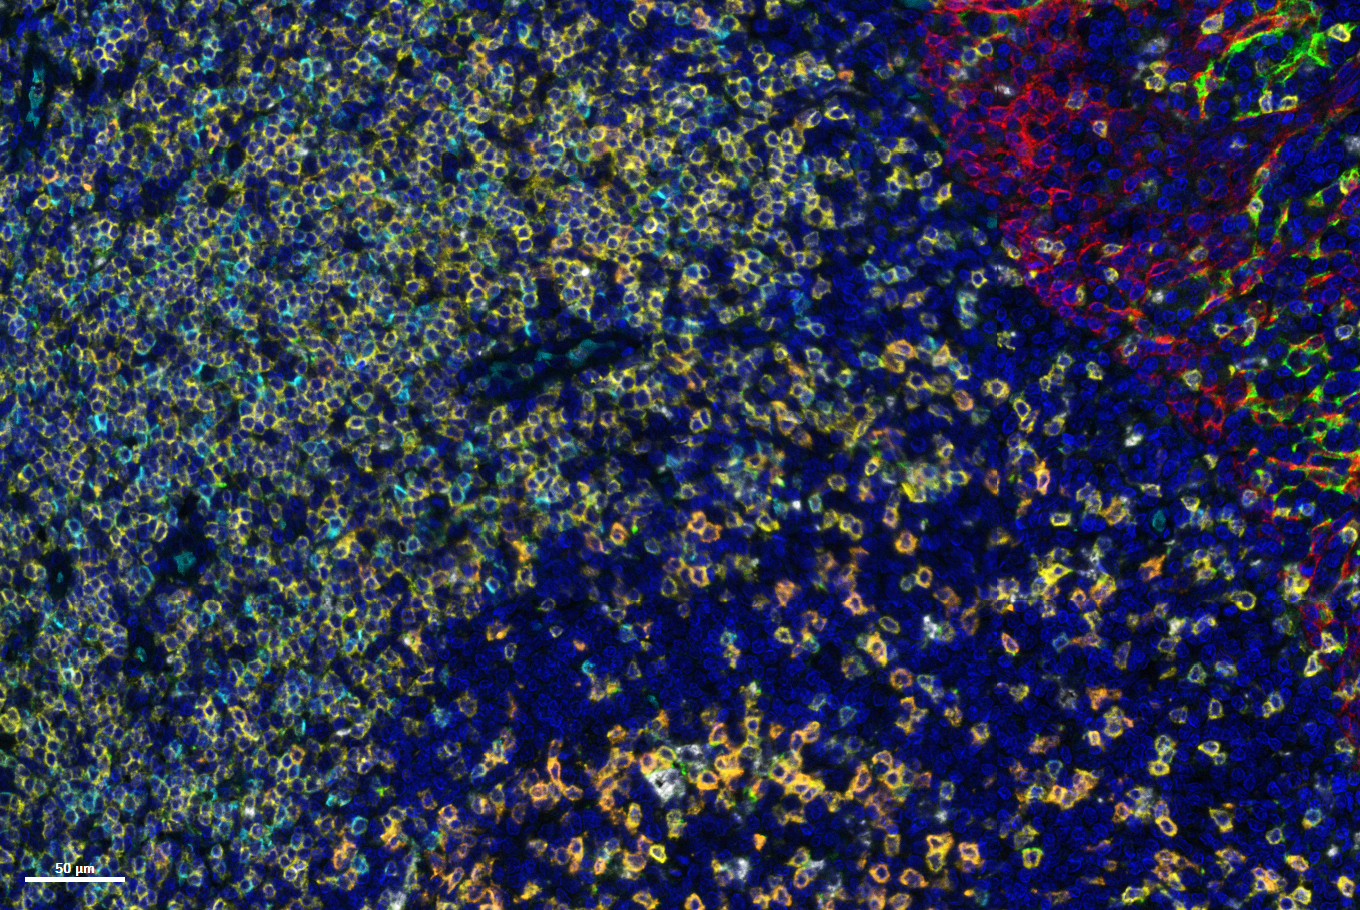

Advanced Pathology Services for Fast, Reliable Data: Histopathology, IHC, IF, and In Situ Hybridization with Automated Precision

H&E and IHC staining

Tissue microarrays are paraffin blocks containing cores from multiple tumor samples, allowing high-throughput analysis for biomarker screening and pathology research.

Explore the complete transcriptome and over 570 protein targets individually or in tandem, utilizing a range of sample inputs including whole tissue sections, tissue microarrays (TMAs), or organoids.